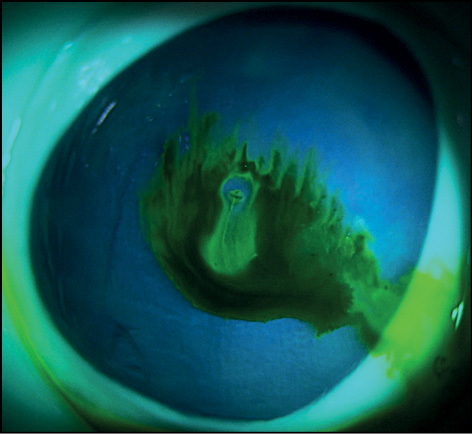

Явление флуоресценции наблюдалось сразу после нанесения красителя на глазную поверхность кадаверных глаз с ОТГ. Флуоресцеин растворялся в вытекающей внутриглазной жидкости и фиксировался по краям раны. Далее отмечалось изменение в окраске потока вытекающей внутриглазной жидкости. Время эксперимента составило 5 секунд (с). В этом временном интервале наблюдали две фазы окрашивания потока вытекающей жидкости. Так, до 2,95 с наблюдали ярко-зелёный поток жидкости (рис. 1, 2). После 2,95 с происходило размывание красителя и разделение основной струи жидкости на несколько потоков с разной степенью интенсивности окрашивания (рис. 3). Через 4,12 с наблюдали уже прозрачный поток вытекающей жидкости в центре и окрашенные зелёные потоки по краям (рис. 4).

Рис. 1. Фаза «ярко-зелёного ручейка» пробы Зейделя сразу после окрашивания флуоресцеином.

Fig. 1. “Bright-green stream” phase of the Seidel test immediately after fluorescein staining.

Рис. 2. Фаза «ярко-зелёного ручейка» пробы Зейделя через 1,32 с после окрашивания флуоресцеином.

Fig. 2. “Bright-green stream” phase of the Seidel test 1.32 s after fluorescein staining.